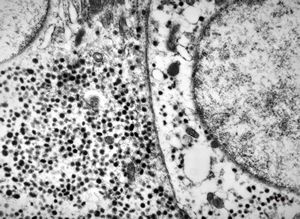

chylomicrons … negative staining